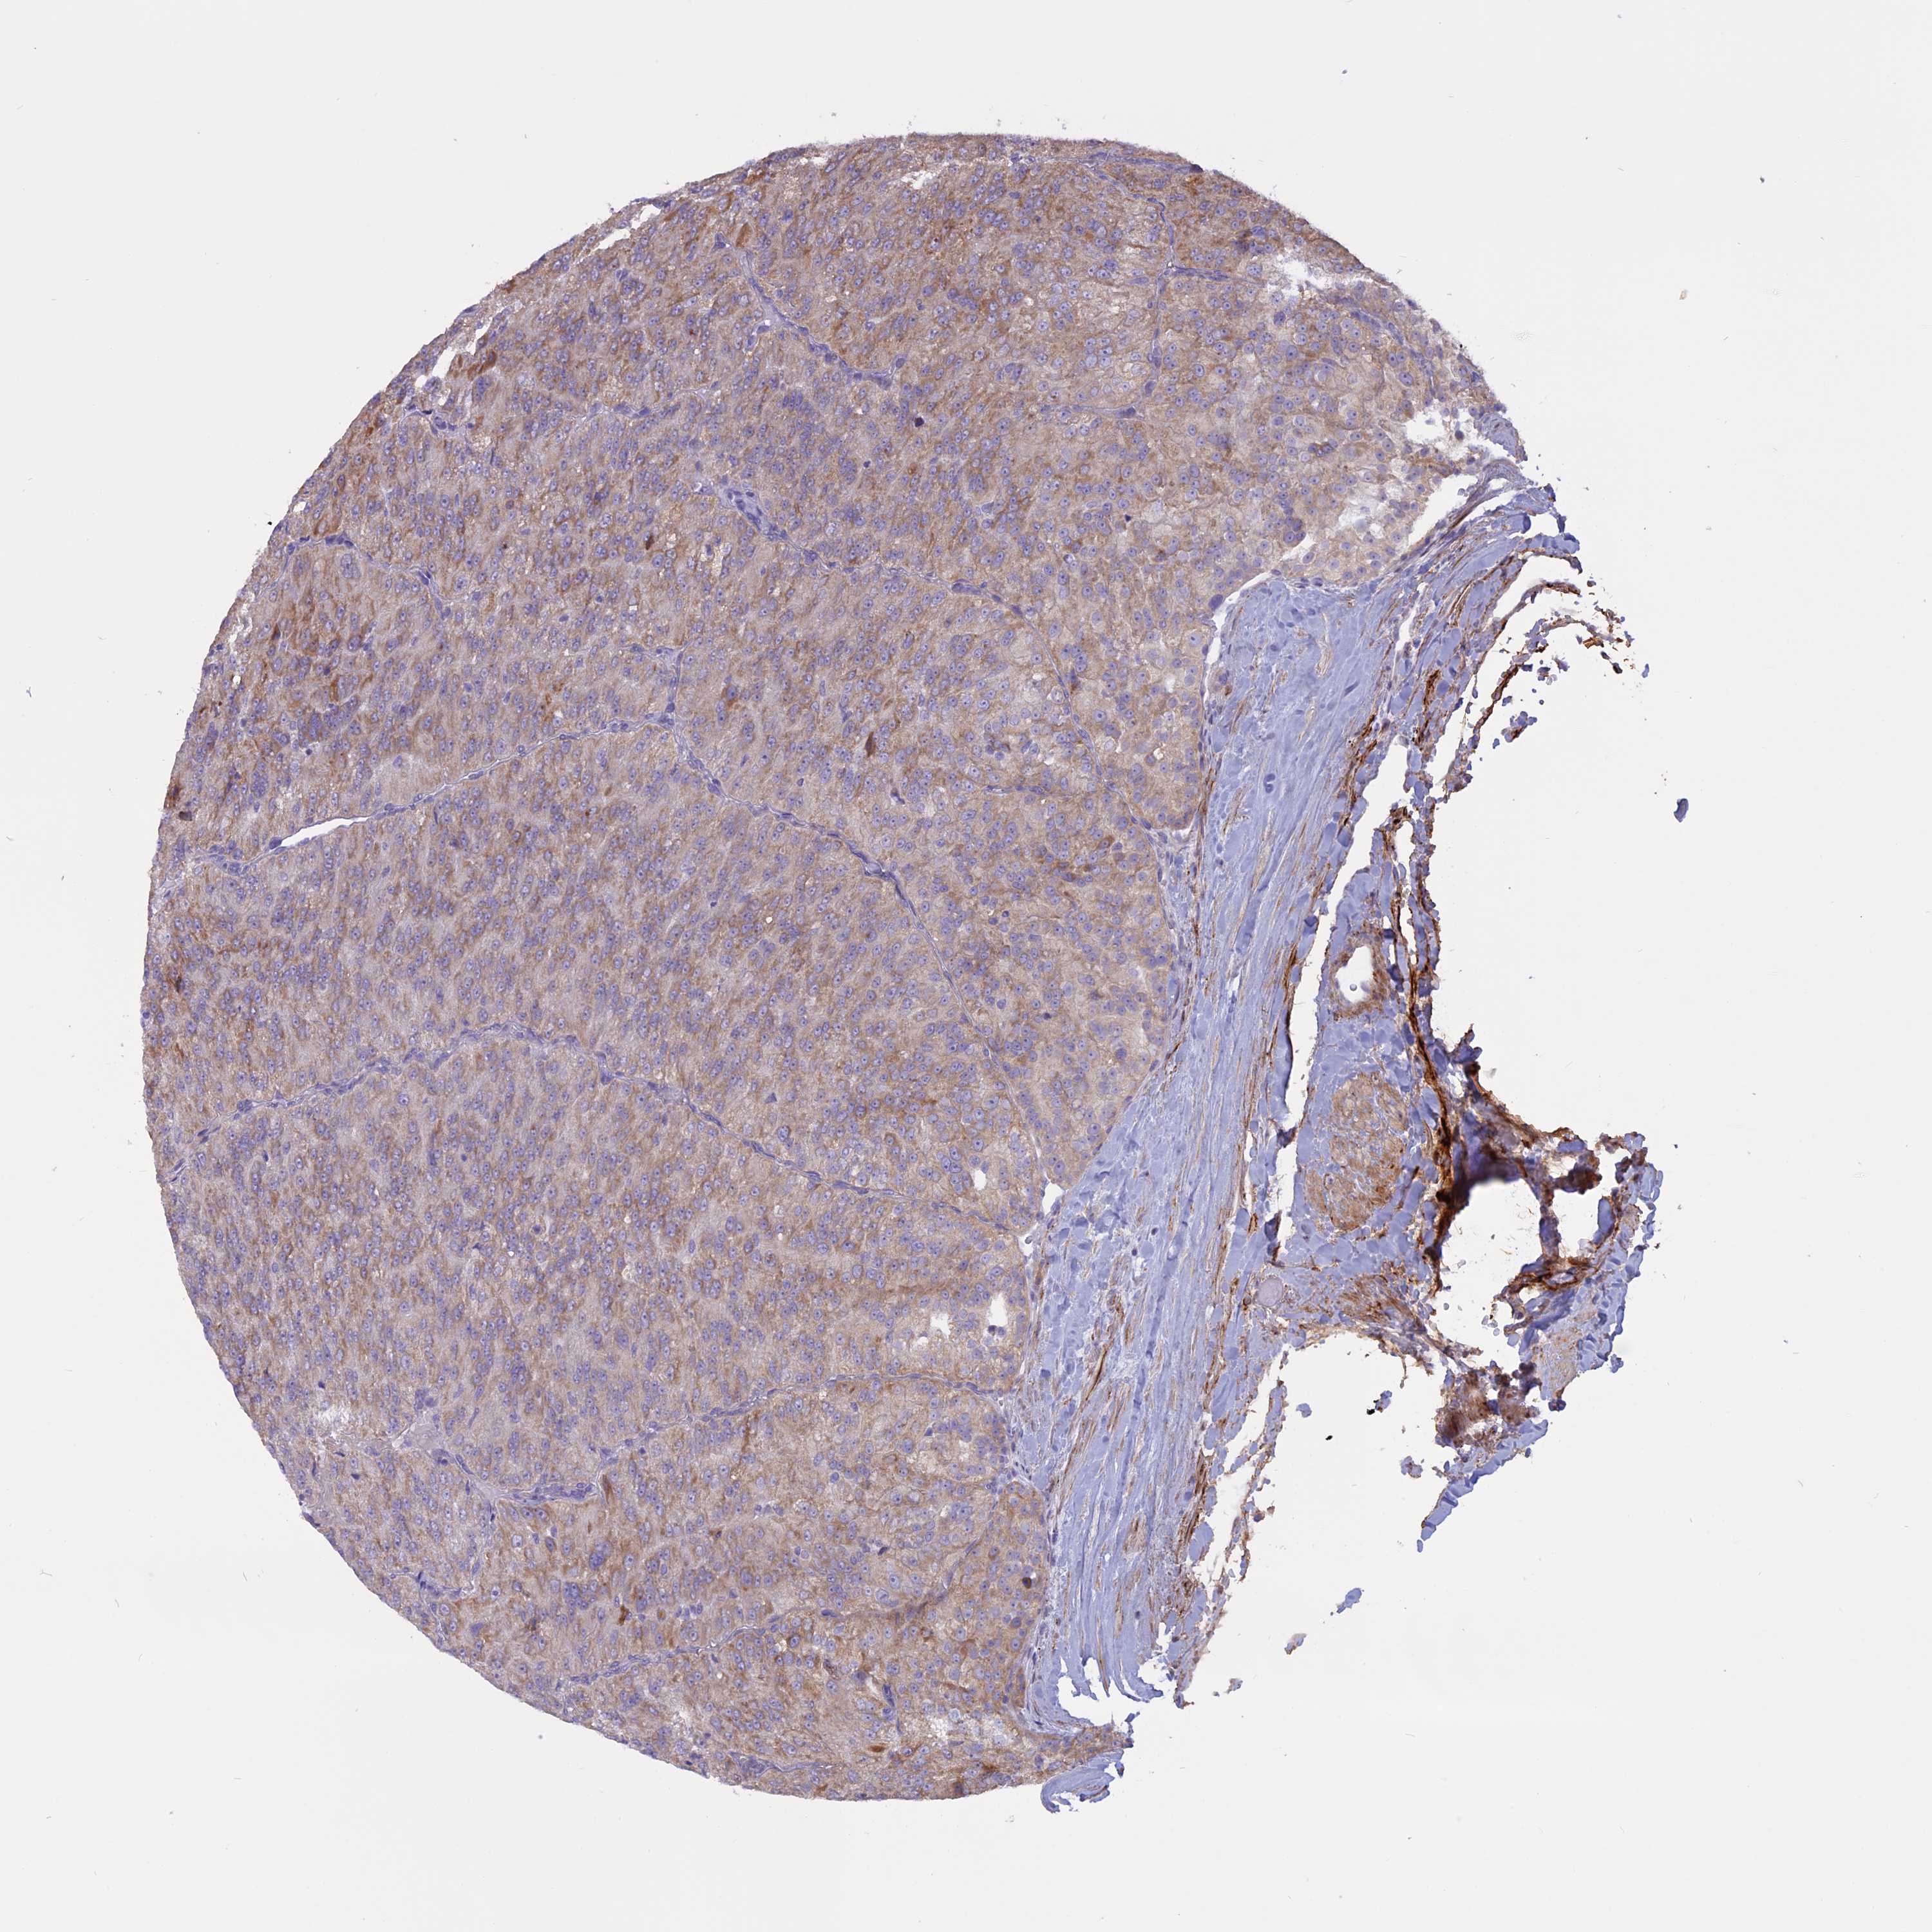

KIDNEY RENAL CLEAR CELL CARCINOMA (TCGA) - Interactive survival scatter ploti

The Survival Scatter plot shows the clinical status (i.e. dead or alive) for all individuals in the patient cohort, based on the same data that underlies the corresponding Kaplan-Meier plots. Patients that are alive at last time for follow-up are shown in blue and patients who have died during the study are shown in red.

The x-axis shows the expression levels (FPKM) of the investigated gene in the tumor tissue at the time of diagnosis. The y-axis shows the follow-up time after diagnosis (years). Both axes are complimented with kernel density curves demonstrating the data density over the axes. The top density plot shows the expression levels (FPKM) distribution among dead (red) and alive patients (blue). The right density plot shows the data density of the survived years of dead patients with high and low expression levels respectively, stratified using the cutoff indicated by the vertical dashed line through the Survival Scatter plot. This cutoff is automatically defined based on the FPKM cutoff that minimizes the p-score. The cutoff can be changed by dragging the vertical line or by entering a cutoff value in the square labeled "Current cut-off".

Under the Survival Scatter plot the p-score landscape (black curve; left axis) is shown together with dead median separation (red curve; right axis). Dead median separation is the difference in median mRNA expression between patients who have died with high and low expression, respectively. It is calculated as follows: median FPKM expression of dead patients with high expression - median FPKM expression of dead patients with low expression. This is intended to aid the user in visually exploring custom cutoffs and the associated p-scores and dead median separation.

Individual patient data is displayed and can be filtered by clicking on one or more of the category buttons on the top of the page. Categories describing expression level and patient information include: high, low, alive, dead, female, male and tumor stages. The scale of the x-axis can be toggled between linear and log-scale by clicking on the "x log" button. Mouse-over function shows TCGA ID, patient information and mRNA expression (FPKM) for each patient.

& Survival analysisi

Kaplan-Meier plots summarize results from analysis of correlation between mRNA expression level and patient survival. Patients were divided based on level of expression into one of the two groups "low" (under cut off) or "high" (over cut off). X-axis shows time for survival (years) and y-axis shows the probability of survival, where 1.0 corresponds to 100 percent.

Survival analysis data not available.

TCGA RNA samplesi

RNA-seq data is reported as average FPKM (number Fragments Per Kilobase of exon per Million reads), generated by the The Cancer Genome Atlas (TCGA) .

Normal distribution across the dataset is visualized with box plots, shown as median and 25th and 75th percentiles. Points are displayed as outliers if they are above or below 1.5 times the interquartile range. FPKM values of the individual samples are presented next to the box plot.

Average pTPM 0.0

Number of samples 521